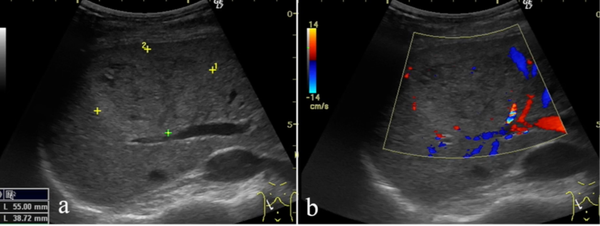

Webinarul include analiza imaginilor relevante și discuții practice asupra cazurilor clinice, pentru o înțelegere aplicată a utilității metodei în diagnosticul urgențelor abdominale ale etajului superior

Sesiunea va include analiza imaginilor relevante și discuții practice asupra cazurilor clinice, pentru o înțelegere aplicată a utilității metodei în diagnosticul urgențelor abdominale ale etajului superior.

Ultrasonografia. Tehnica de explorare. Specific

Ultrasonografia ficatului

Colecist și căi biliare

Studii de caz și imagini comentate